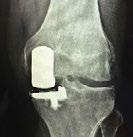

ORTHONEURO

Heather Benjamin 6785 Bobcat Way, Ste. 300 Columbus, OH 43016 614-890-6555 orthoneuro.com